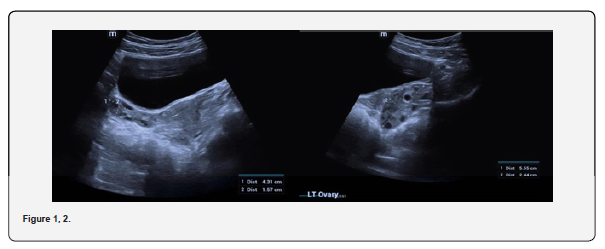

The patient is a 12-year-old girl who presented to emergency department with severe left-sided abdominal pain associated with persistent vomiting for the past two days. On physical examination left flank tenderness was noted with radiation to suprapubic area, there was no diarrhea or fever. Pelvic ultrasound with Doppler demonstrated bilaterally enlarged ovaries with small follicles with a markedly enlarged left ovary showing reduced vascularity and no evidence of identifiable ovarian cyst (Figures 1-4). Magnetic resonance imaging (MRI) demonstrated bilateral ovarian enlargement with multiple small follicles, assuming polycystic ovarian morphology. The left ovary was significantly enlarged, positioned posterior to the uterus and showed stromal edema with decreased post-contrast enhancement compared to contralateral side, findings consistent with ovarian torsion (Figures 5-10).

Common ultrasound findings include ovarian enlargement, peripheral displacement of follicles, heterogenous ovarian echotexture due to edema and reduced or absent blood flow, However, normal or preserved blood flow does not exclude ovarian torsion, particularly in cases of intermittent torsion. Previous studies have reported that the presence of Doppler flow on ultrasound cannot be used to exclude ovarian torsion whereas the absence of Doppler flow represents a significant diagnostic marker [4]. Emergency medicine literature similarly reports that Doppler flow may be present in cases of ovarian torsion and should not be used alone to exclude the diagnosis [5]. In the present case, ultrasound showed ovarian enlargement with decreased blood flow, which raised suspicion for torsion despite the absence of a clearly identifiable ovarian cyst or mass.